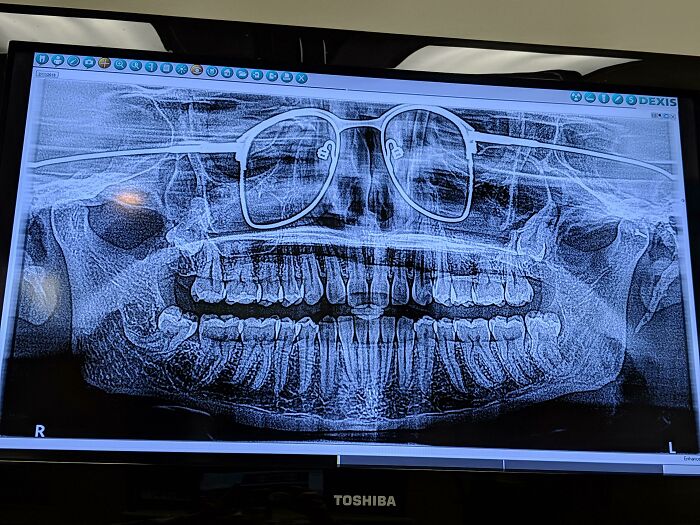

«Мне делали панорамный снимок челюсти и я забыл снять очки»